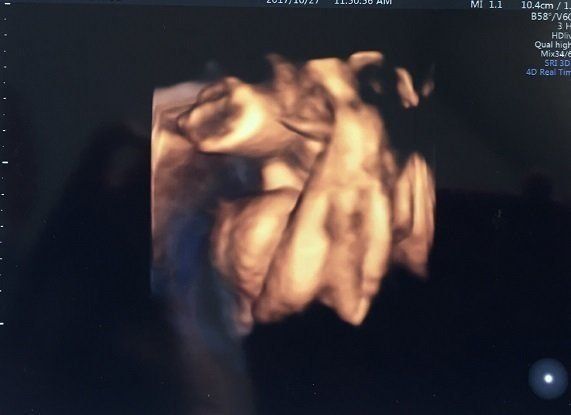

妊娠26週目のエコー写真 お腹の赤ちゃんの性別が判明!

紛れもなく男の子のシンボルですよね! 先生が言う前に「先生、ついていますよね、これ」と私が言うほどに一瞬でわかりました。先生も「99.9%男の子ですね。これで違っていたら、ごめんね」と、笑っておっしゃるほど。判断しやすい性別判断となりました。

こちらは別角度から見た男の子のシンボルです。1人目は女の子だったので、女の子のときとは全く違うエコーに感動してしまいました。女の子はなかなかはっきり言ってもらえませんでしたから。